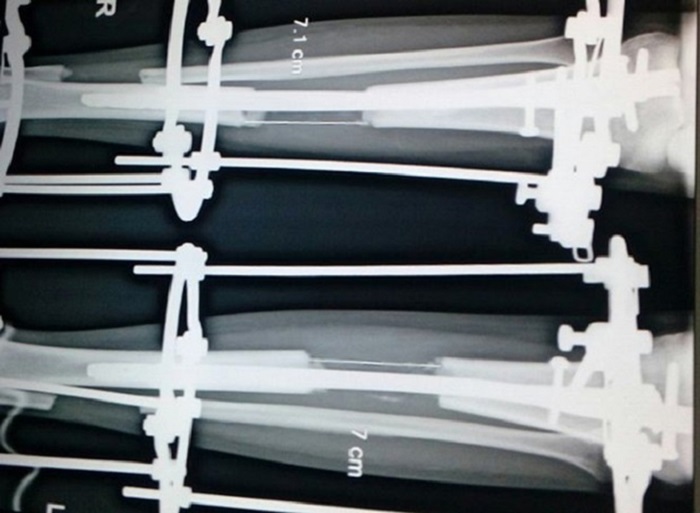

3В Индии начался настоящий бум на операции по увеличению роста. Молодые девушки готовы терпеть боль и длительный физический дискомфорт, только бы стать немного выше. Всё потому, что одним из канонов красоты в Индии считается стройное тело и высокий рост. Так что несколько лишних сантиметров в жизни человека могут стать решающими. Это касается и карьеры, и создания семьи, и положения в обществе.

Чаще всего на такие операции решаются девушки. Индийцы даже продают доставшиеся в наследство участки земли, чтобы их дети могли стать выше хотя бы на 7-8 сантиметров.

Хирурги ломают абсолютно здоровые кости, ставят на них специальные скобы, и пациенты по нескольку месяцев ждут, пока кости срастутся, постоянно испытывая сильную боль.

Однако самое неприятное в этих операциях как раз не боль, а то, что пациент может навсегда остаться калекой, если попадет на стол к хирургу-шарлатану. В Индии эта отрасль хирургии совершенно новая и законодательно никак не урегулирована, поэтому «удлинением» ног может заниматься любой врач. Хирургом ему для этого быть совсем не обязательно...